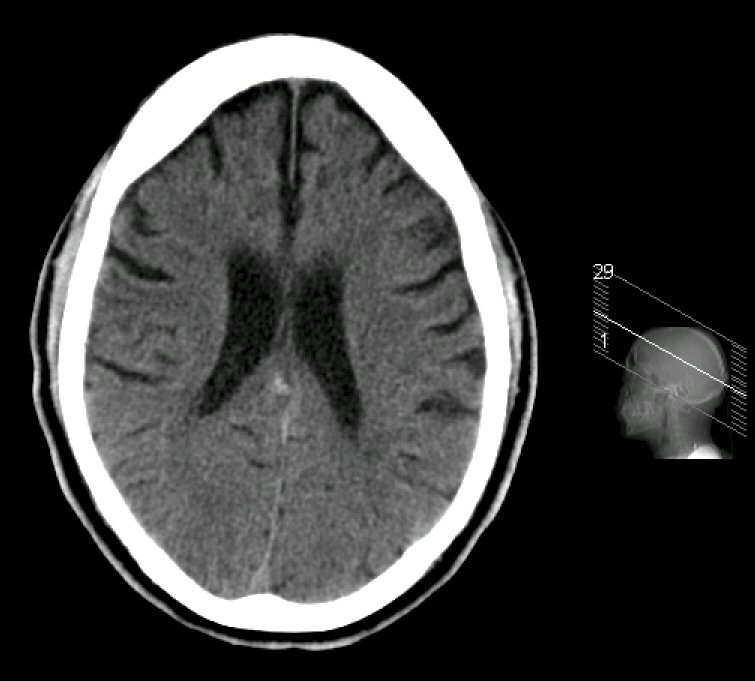

CT lateral ventricles Ct Anatomy Of Ventricular System the ventricular system in the brain is a series of interconnecting spaces and channels within the brain composed. the cerebral ventricular system is made up of 4 ventricles that include 2 lateral ventricles (1 in each cerebral hemisphere), the third. the brain is surrounded by cerebrospinal fluid ( csf) within the sulci, fissures and basal cisterns. Web. Ct Anatomy Of Ventricular System.